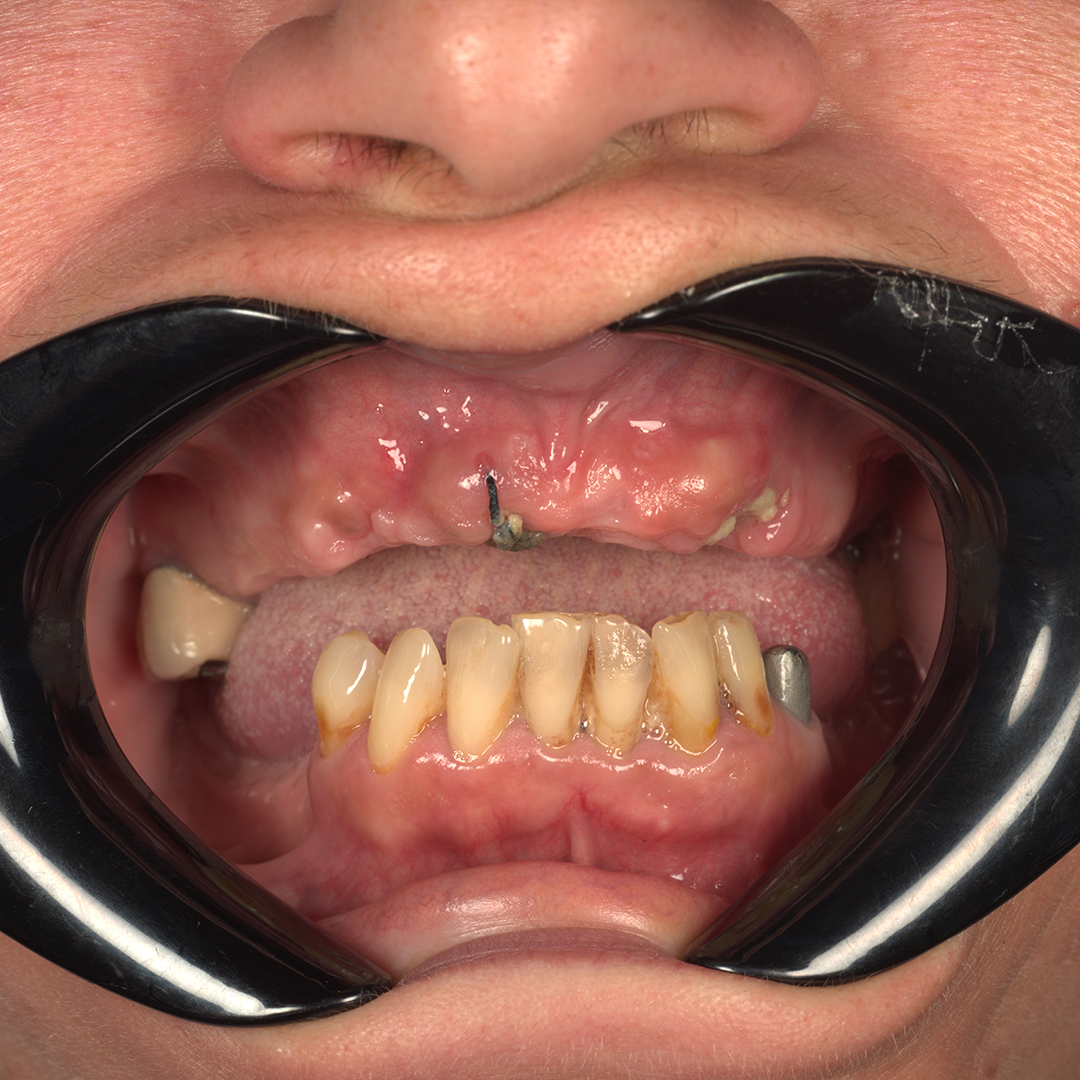

Înainte / După

exemplu (cu acordul pacientului)

Înainte - caz real

Înainte

După - caz real

După

Cazuri Clinice Reale

Rezultate obținute în clinica noastră. Imaginile sunt prezentate cu acordul pacienților.

Caz 1 - Înainte Reabilitare Totală Înainte

Caz 1 - După După

Pacient M.A. (58 ani)

Restaurare funcțională completă cu lucrare fixă.